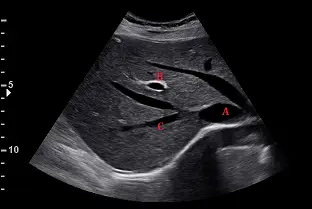

下圖為肋骨弓下緣之超音波掃描影像,其編號A、B、C的解剖位置,依序應為下列何者?

這是一張肝臟的肋骨弓下緣橫切面超音波影像(Subcostal transverse/oblique view),探頭向頭側(Cephalad)傾斜以觀察肝靜脈匯流處。

- 標示A:位於肝臟後方的巨大無回音(Anechoic)管狀構造,且可見多條靜脈匯流進入其中,此為下腔靜脈(Inferior Vena Cava, IVC)。

- 標示B:位於肝臟實質內的管狀構造,其管壁呈現明顯的高回音(Hyperechoic,較亮的白邊)。這是因為門靜脈系統周圍有結締組織(Glisson's capsule)包覆延伸,此為**門靜脈(Portal Vein)**分支的典型超音波特徵。相對而言,肝靜脈的管壁極薄,通常不會有明顯的高回音邊緣。

- 標示C:為匯流至下腔靜脈的肝靜脈之一。在標準的腹部橫切面掃描設定下(探頭指標朝向病患右側),螢幕的左側代表病患的右側,螢幕的右側代表病患的左側。標示C位於影像的左下方(病患的右側),因此這是右肝靜脈(Right Hepatic Vein)。其上方相鄰的是中肝靜脈(Middle Hepatic Vein),而位於最右側(病患左側)的則是左肝靜脈(Left Hepatic Vein)。這三條靜脈匯入下腔靜脈的典型影像在臨床上常被稱為「花花公子兔星號(Playboy Bunny sign)」。

根據影像解剖學特徵,血管A收集肝臟血流並位於較深層,為下腔靜脈 (IVC)。血管B管壁明亮,符合門靜脈 (Portal Vein) 的超音波特性。血管C位於螢幕左側,對應病患解剖構造的右方,匯流至下腔靜脈的此血管即為右肝靜脈 (Right Hepatic Vein)。因此,正確答案為 (C)。